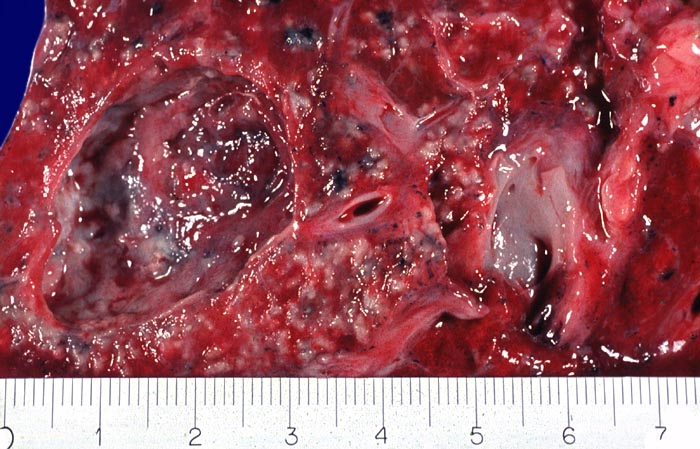

Das morphologische Bild ist äusserst variabel. Je nach Abwehrlage, Art und Geschwindigkeit der Ausbreitung entstehen unterschiedlich grosse, teils geschichtete Herde mit unterschiedlichem Grad an Epitheloidzellreaktion, zentraler Nekrose bzw. Vernarbung. Rein produktive Granulome ohne Nekrosen sind Zeichen guter Abwehrlage. Der Begriff Verkäsung bezieht sich auf den makroskopischen Aspekt von Nekrosen, der an Frischkäse erinnert. Exsudative nekrotisierende Granulome entstehen bevorzugt bei schlechter Abwehrlage. In späteren Stadien der Lungentuberkulose unterscheidet man produktive Phthisen mit azinös nodösen Gruppen von bronchogen entstandenen gering verkäsenden Streuherden (Präparat), zirrhotische Phthisen mit gering verkäsenden stark vernarbenden Herden und exsudative Phthisen bei schlechter Abwehrlage. Bei letzterer steht die Verkäsung im Vordergrund. Die bakterienreichen Herde entstehen teils hämatogen, teils bronchogen. Verkäsende Herde sind Ausgangspunkt für die Kavernenbildung. Kavernen stellen die wichtigste Quelle für die bronchogene Streuung dar.

Makroskopie